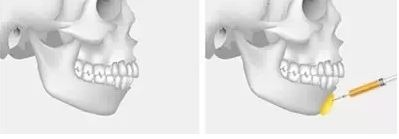

玻尿酸丰下巴

打玻尿酸丰下巴,玻尿酸填充剂被打入下巴后会与人体原有成分融合,整形医生再根据受术者个人面部轮廓捏出美观的下巴。

优点:采用打玻尿酸的方式,不影响生活和工作。